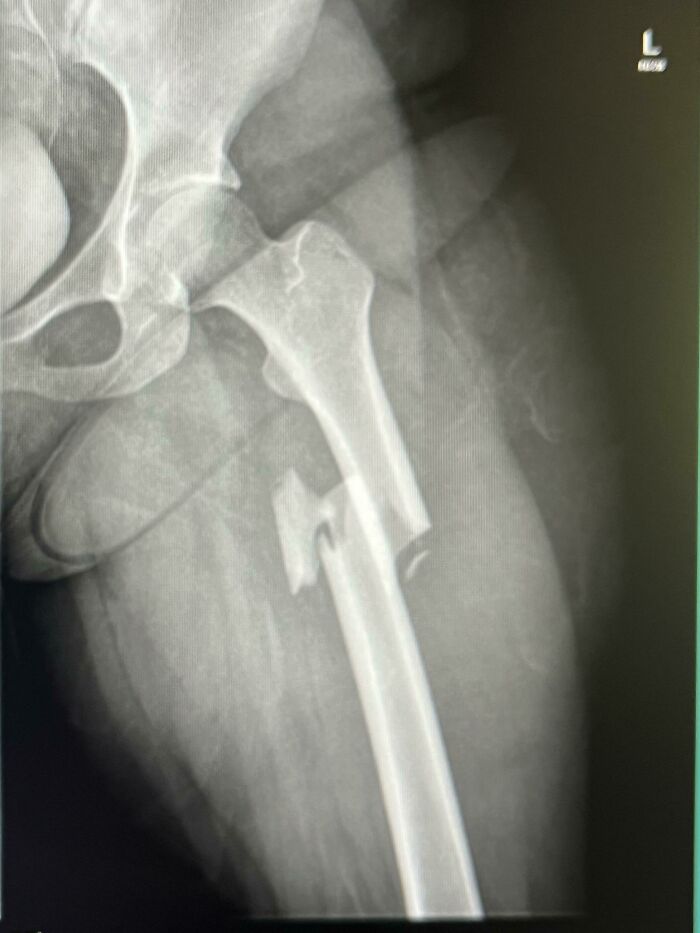

Free Fall From 30 Ft

You don't need 30ft for this. I present you a free fall from my bike that got stuck in some streetcar tracks :D That sucked. A LOT! Oberschenk...2ccaa5.jpg